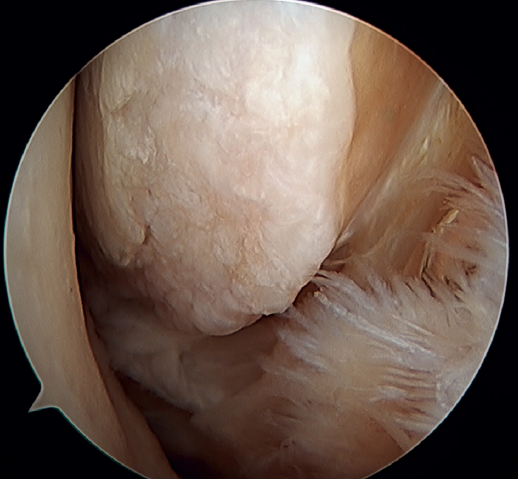

The main indication for this repair is rupture of the upper fascicle of the ATFL from its fibular insertion, with good tissue quality of the remaining ligament (Figure 3).